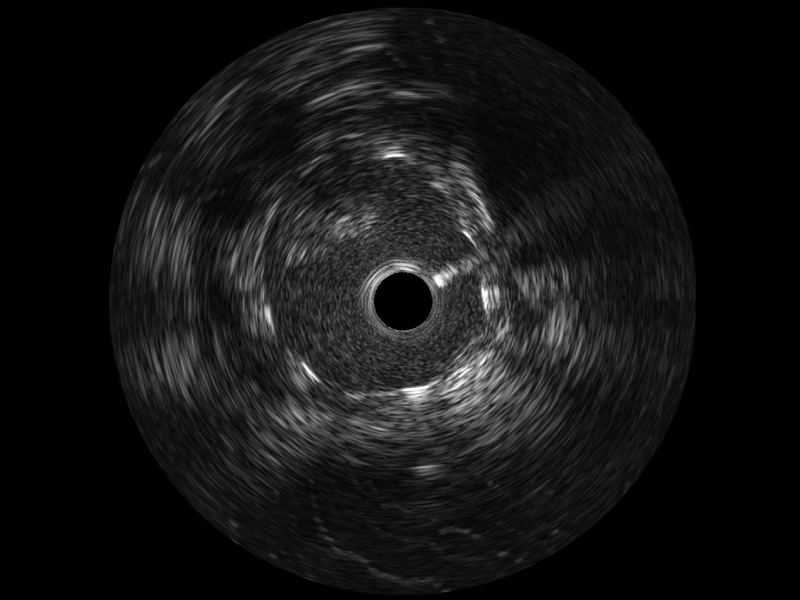

• 传统IVUS图像

对比传统IVUS导管成像,milan米兰宽频IVUS图像的近场支架梁显影更细腻,远场中膜外血管仍清晰可辨,兼顾远中近,兼顾分辨力与穿透深度